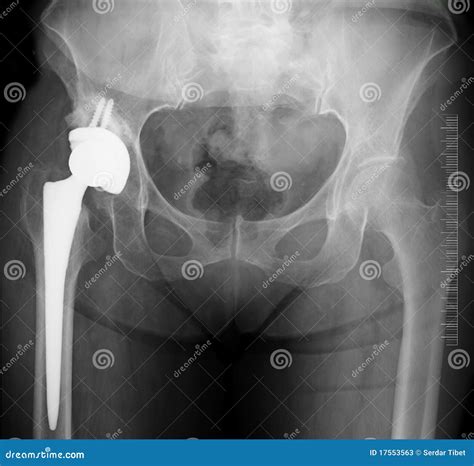

A Double Hip Replacement is a surgical procedure where both hip joints are replaced with artificial implants. This is often recommended for patients who experience severe pain and limited mobility in both hips. The procedure aims to relieve pain, improve joint function, and enhance the overall quality of life.

• Implant Placement: The artificial hip components are placed and secured in position. The femoral component is inserted into the thighbone, and the acetabular component is placed in the hip socket.